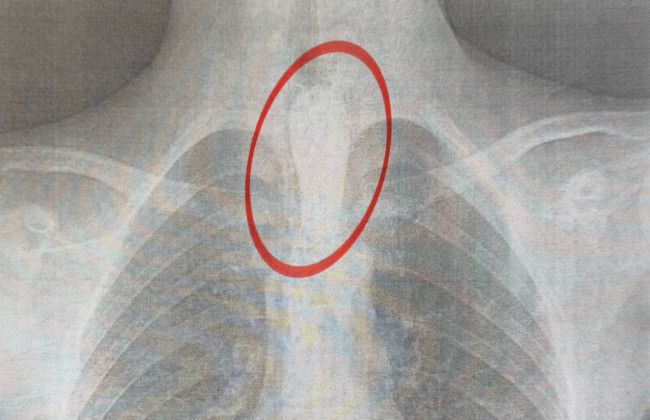

Инцидент произошел, когда после употребления пищи у подростка внезапно возникли трудности с глотанием - он не мог даже проглотить слюну. Медики обнаружили, что инородное тело остановилось на одном из естественных сужений пищевода, из-за чего ребенок испытывал сильный дискомфорт и недостаток воздуха.

Хирургическое вмешательство началось в два часа ночи. Специалисты Центра детской медицины провели ригидную эзофагоскопию, которая длилась около часа. Кусок мяса удаляли осторожно, поэтапно, чтобы не повредить стенки органа. По словам врачей, такие операции требуют особой точности, чтобы избежать осложнений, в частности перфорации пищевода.